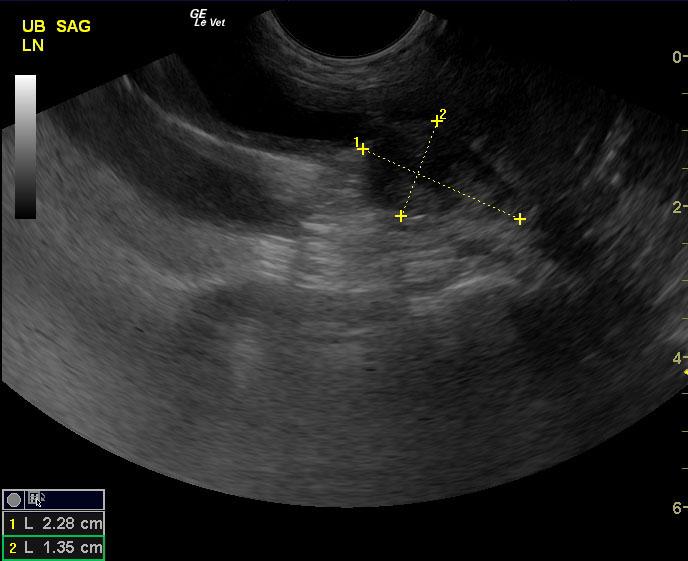

A 9-year-old NM canine mix was presented for evaluation of hematuria and urinating in the house that has not responded to a course of Baytril. Red and white blood cells were evident on urinalysis.